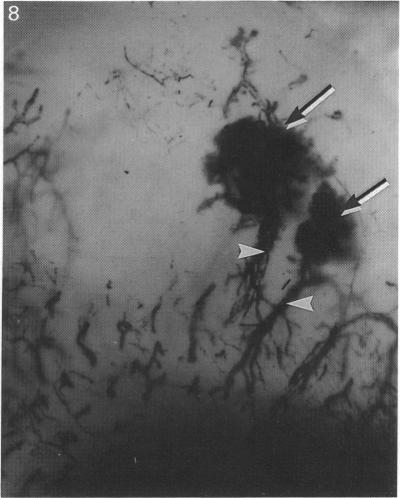

Epiphyseal centres of ossification in the bones forming the elbow joints of pigs between one day and 15 weeks of age were examined radiographically, macroscopically, mesoscopically and microscopically. Thoracic limbs from 39 pigs were perfused with India ink or silicone rubber injection compound and the bones were dissected free of soft tissues. The humerus, ulna and radius were fixed in formalin or ethyl alcohol and then cleared by the modified Spalteholz technique. Bones were radiographed, examined grossly, and then cut into slabs for mesoscopical evaluation. Foci considered to be calcifying within cartilaginous anlage were selected for microscopical examination. It was concluded that the epiphyseal centre of ossification develops at different times in different sites in the bones forming the elbow joint. Centres of ossification are initiated when foci of chondrocytes adjacent to one side of a cartilage canal undergo hypertrophy and the inter-territorial matrix becomes calcified. Osteogenesis then proceeds in the calcified focus, presumably with osteoprogenitor cells that originate within the cartilage canals. Subsequently, each epiphyseal centre of ossification enlarges by one of two methods. Firstly, the layer of cartilage adjacent to the centre undergoes endochondral ossification, thus allowing for the circumferential growth of the epiphyseal centre of ossification. Secondly, foci of calcification develop adjacent to the ends of cartilage canals near the epiphyseal centre of ossification and eventually the focus of calcification coalesces with the developing epiphyseal centre of ossification, thus establishing a new ossification front. Endochondral ossification continues at the periphery of the mass of bone. Mesoscopical examination is more useful than radiographical evaluation for identifying small foci of calcification which precede epiphyseal centres of ossification.

对1日龄至15周龄猪肘关节骨骼的骨骺骨化中心进行了放射学、大体、中观和微观检查。对39头猪的胸肢灌注印度墨水或硅橡胶注射复合物,然后将骨骼从软组织中分离出来。将肱骨、尺骨和桡骨固定在福尔马林或乙醇中,然后采用改良的斯帕尔托霍尔茨技术进行透明处理。对骨骼进行放射照相、大体检查,然后切成薄片进行中观评估。选择软骨原基内被认为正在钙化的病灶进行微观检查。得出的结论是,肘关节骨骼不同部位的骨骺骨化中心在不同时间发育。当软骨管一侧相邻的软骨细胞灶发生肥大且细胞间基质钙化时,骨化中心开始形成。然后在钙化灶中进行骨生成,推测是由软骨管内起源的骨祖细胞进行的。随后,每个骨骺骨化中心通过两种方法之一扩大。首先,与中心相邻的软骨层进行软骨内骨化,从而使骨骺骨化中心进行圆周生长。其次,在靠近骨骺骨化中心的软骨管末端附近出现钙化灶,最终钙化灶与正在发育的骨骺骨化中心融合,从而形成新的骨化前沿。软骨内骨化在骨块的周边继续进行。对于识别在骨骺骨化中心之前的小钙化灶,中观检查比放射学评估更有用。